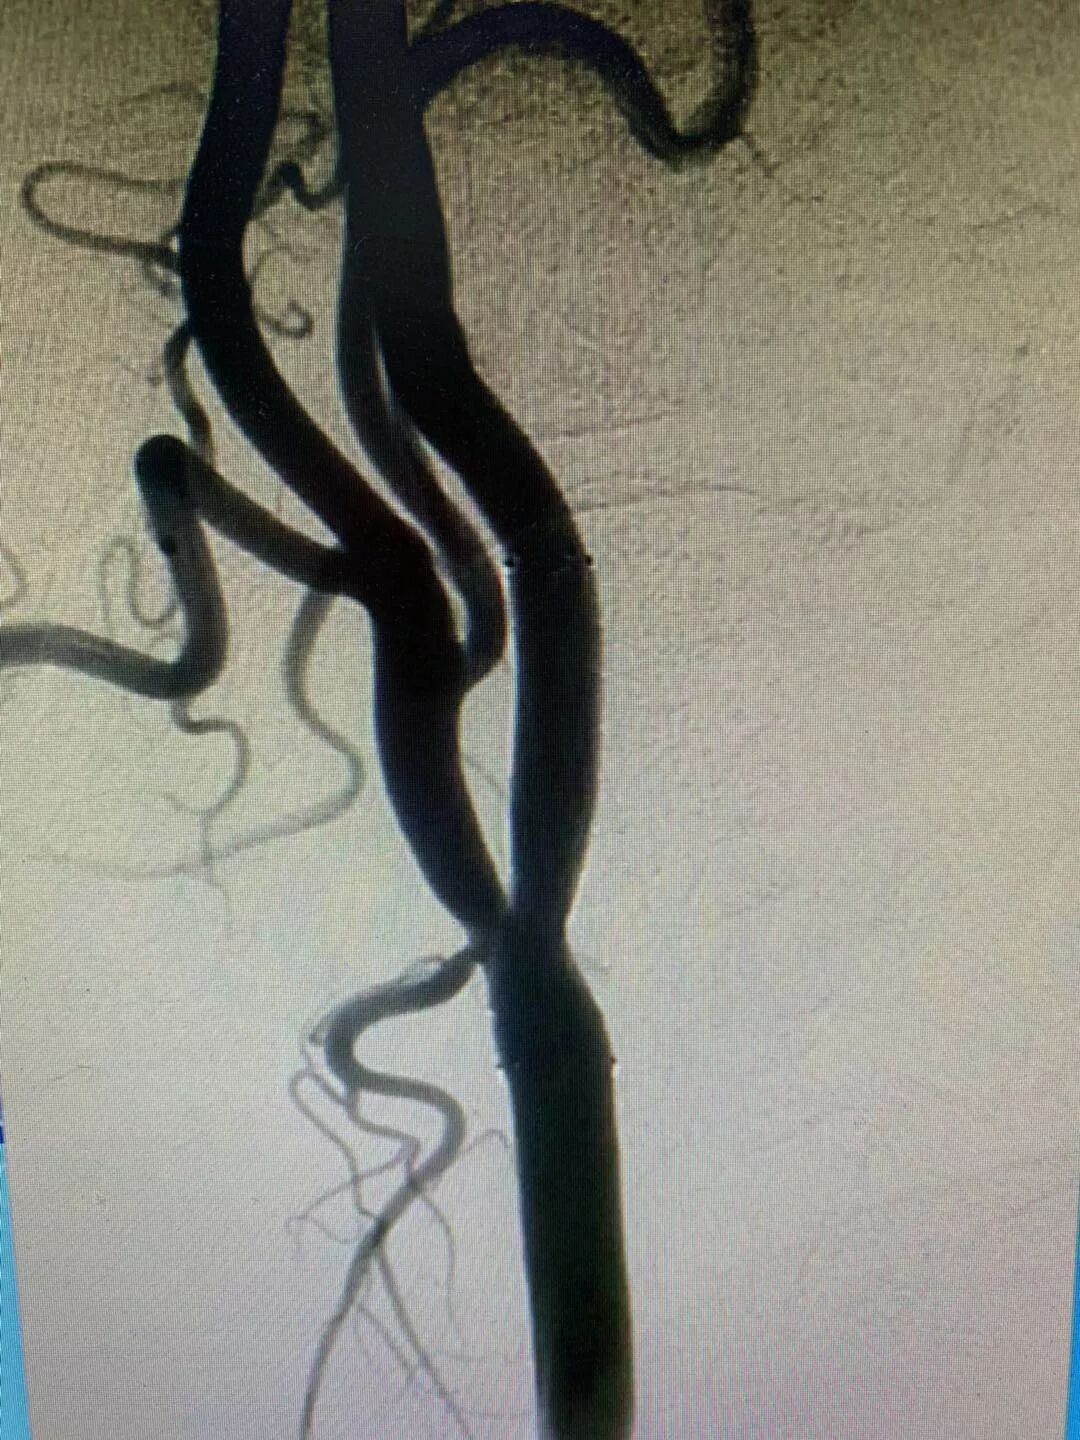

5月25日一位突发言语不清的任某入住郑州中康医院神经内科一病区。入院后医师给予完善各项检查,头部磁共振检查,结果提示:双侧基底节腔隙性脑梗塞。5月29日在郑州中康医院介入导管室进行了脑血管造影,造影结果提示:右侧颈内动脉起始部重度狭窄。

图片

(术前右侧颈内动脉造影)

颈动脉狭窄临床上主要表现为脑和眼的缺血症状。病变累及大脑前循环供血动脉即颈总、颈内动脉者,可有头晕、头痛、晕厥、一过性黑朦、失明等症状;但其典型临床症状为短暂性脑缺血,即一过性肢体无力和麻木,以及短暂性偏瘫发作。病变累及大脑后循环及椎动脉者可出现椎基底动脉缺血表现,如眩晕、晕厥和恶心等。严重者可发生卒中即脑梗死。

医师建议行介入手术治疗,于6月4日下午召开了术前讨论,经讨论分析后,患者情况适合进行手术治疗,与家属沟通后,家属同意手术治疗。

(颈内支架植入后,狭窄明显改善)

6月5日上午,由介入导管室张少雷主任亲自主刀,在介入导管室行“右侧颈内动脉起始处球囊扩张术及支架植入术”,手术历时1个半小时,手术过程顺利,患者愈后良好,家属表示非常满意。